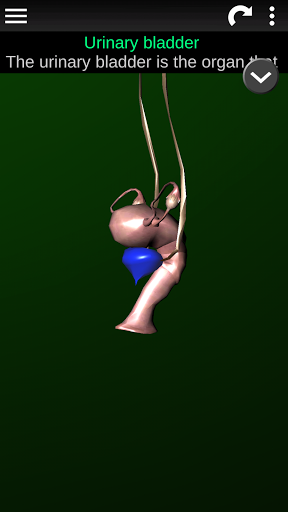

* Beschrijvingen van elk orgel.

Deze app is ontworpen als aanvulling op de studie van anatomie in verschillende onderwijs-, gezondheidszorg- en culturele omgevingen.

Praktische, nuttige en waardevolle anatomische informatie binnen handbereik.